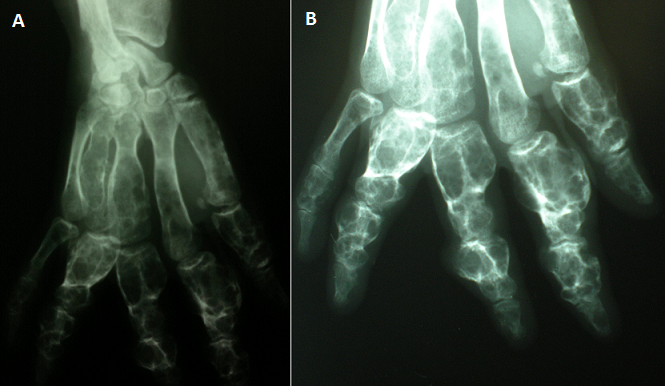

Le syndrome de Maffucci est une affection très rare caractérisée par l'association de chondromes multiples et d'hémangiomatose des parties molles. Les os les plus atteints dans cette affection sont par ordre de fréquence décroissant: les os de la main, les os des pieds, le fémur, les os de la jambe, le bassin, l'humérus et les os de l'avant-bras. Le risque majeur du syndrome de Maffucci reste la transformation chondrosarcomateuse. Le traitement du syndrome de Maffucci reste limité aux antalgiques et aux interventions chirurgicales de résection tumorale et de correction des déformations. Nous rapportons le cas d'un patient de 21 ans, ayant consulté pour des déformations des deux mains évoluant depuis l'enfance. L'examen clinique a mis en évidence des déformations avec des tuméfactions des doigts associés à des hémangiomes cutanés au niveau du thorax et du bras droit. Les radiographies standard ont montré des multiples lacunes anarchiques soufflant les corticales et intéressant toutes les phalanges et les métacarpiens. La biopsie a permis de poser le diagnostic de chondrome et l'association de chondromes multiples et d'angiomes cutanés a fait évoquer le diagnostic de syndrome de Maffucci. Le traitement avait consisté en la résection chirurgicale des chondromes les plus saillants des deux mains. L'évolution était marquée par la récidive motivant une reprise chirurgicale. Le syndrome de Maffucci est une entité très rare, caractérisée par l'association d'une enchondromatose multiple et d'une hémangiomatose. Nécessitant une surveillance de prés en raison du risque de dégénérescence sarcomateuse aussi bien des lésions osseuses que cutanées.